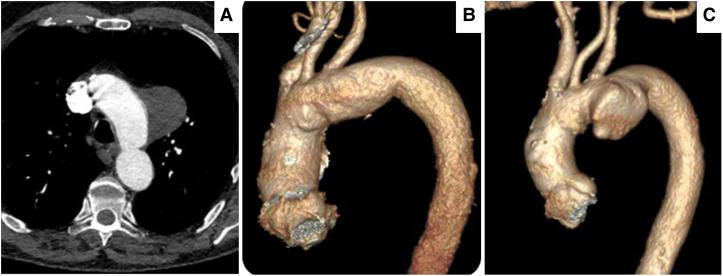

We present a 66-year-old male initially referred with a 7.35 cm giant thoracic aortic arch diverticulum (TAD). It was initially discovered incidentally as a 2.1 cm type 3 Salomonowitz; however, it subsequently increased to 7.36 cm following the third COVID-19 infection with cytokine storm. He underwent a right-to-left carotid necklace C-shaped configuration cross-over bypass using an 8 mm ringed Dacron silver graft. Six weeks post-bypass, the patient underwent a successful repair of TAD using the NEXUS-Endospan-Artivion system (Artivion™, GA 30144, USA), employing a double inner branch to the innominate and left subclavian artery through a single groin approach. Postoperatively, he recovered fully without any neurological or cardiovascular issues with no signs of endoleaks, graft migration, or separation.

我们报告一名66岁男性,最初因一个7.35厘米的巨大胸主动脉弓憩室(TAD)前来就诊。它最初偶然被发现为一个2.1厘米的3型萨洛莫诺维茨憩室;然而,在第三次感染新冠病毒并出现细胞因子风暴后,它随后增大到了7.36厘米。他接受了使用8毫米带环涤纶银移植物的右向左颈动脉链C形交叉旁路手术。旁路手术后六周,患者使用NEXUS - Endospan - Artivion系统(美国Artivion™,GA 30144)通过单腹股沟入路对无名动脉和左锁骨下动脉采用双内分支成功修复了TAD。术后,他完全康复,没有任何神经或心血管问题,也没有内漏、移植物移位或分离的迹象。